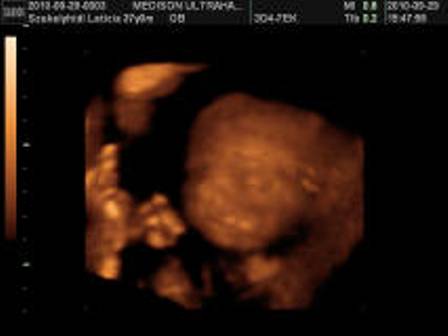

Zsófika meg csak növöget hál'Istennek, már megismeri Apuka közelségét, ficánkol is neki rendesen.